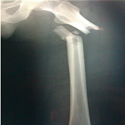

Association très rare: fracture de la diaphyse fémorale associée à une fracture de Hoffa homolatérale

Issam Elouakili, Younes Ouchrif

PAMJ. 2014; 19: 223. Published 29 October 2014